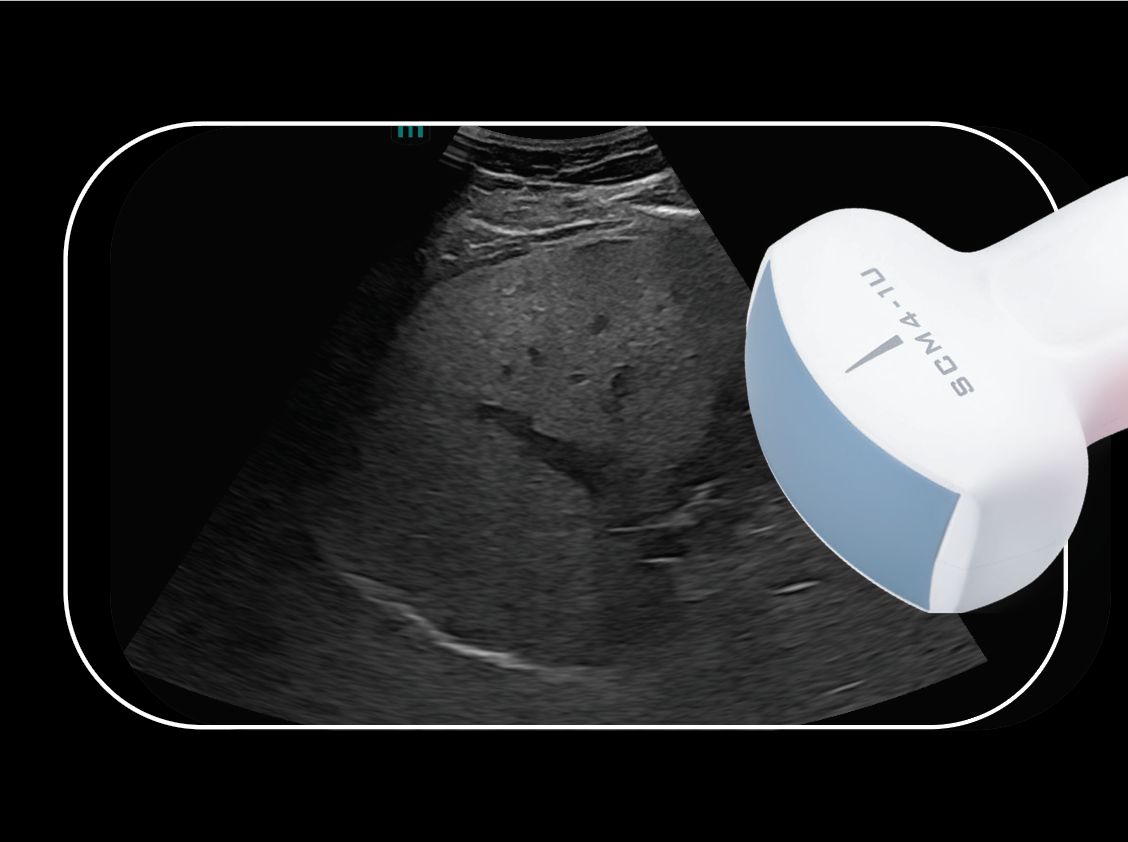

A closer look at just a few of our transducers: